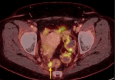

Figure 7

Figure 7. Axial PET with RT planning overlay demonstrating dose (as color wash) from 30 Gy (in blue) to 47.6 Gy (red), which is the prescription dose to the pelvis, primary, and uterus.

RT: radiation tomography; PET: positron emission tomography